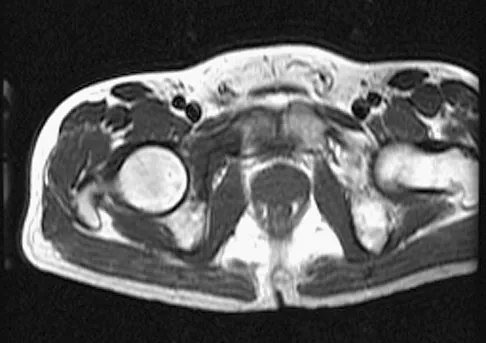

A 28-year-old man has left knee pain after a snow skiing accident. The MRI scan shown in Figure 47 reveals which of the following?

Explanation